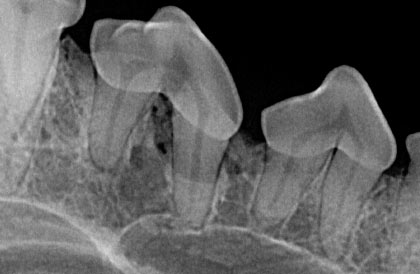

The Importance Of Dental Radiographs Hillcrest Animal Hospital

The Importance Of Dental Radiographs Hillcrest Animal Hospital from www.hillcrestanimalhospital.ca